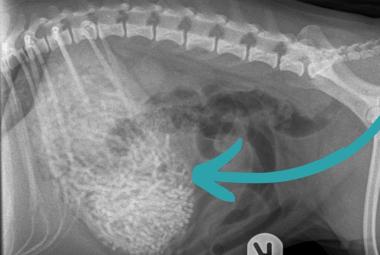

Porodica šokirana onim što su veterinari pronašli u stomaku njihovog psa